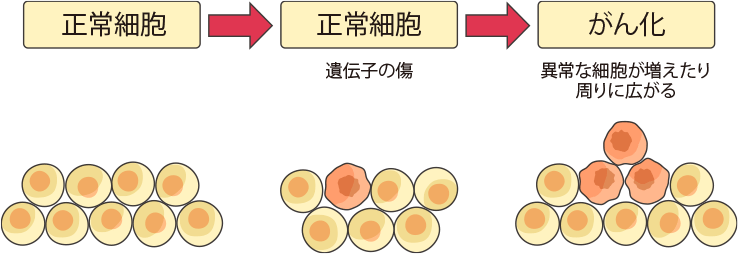

がんはどうやってできるの?

遺伝子が傷つき細胞の増殖の調節がコントロールできなくなる

人間の体は、たくさんの細胞から作られており、細胞が分裂して数を増やしながら、さまざまな形や働きをもつ組織や臓器が作られていきます。

正常な細胞は、増え続けたり(増殖)、それを止めたりを、体の状態にあわせて調節しています。いくつかの遺伝子はこの増殖を調節する働きをもっています。

ところが、何らかの原因で遺伝子が傷つき、異常が起こると、この増殖の調節がコントロールできなくなってしまいます。

異常な細胞が増え続けると「がん」になる

わたしたちの体には、もともと遺伝子の異常を見つける仕組みが備わっていて、傷ついた遺伝子を修復したり、異常な細胞を排除したりして正常な状態を維持しています。

しかし、遺伝子が傷ついた異常な細胞の一部は、体からの命令を無視してどんどん増えたり、周りに広がったりする性質をもつようになります。これが、「がん細胞」です。がん細胞が何年もかけて増え続け、がんとして発見されると考えられています。